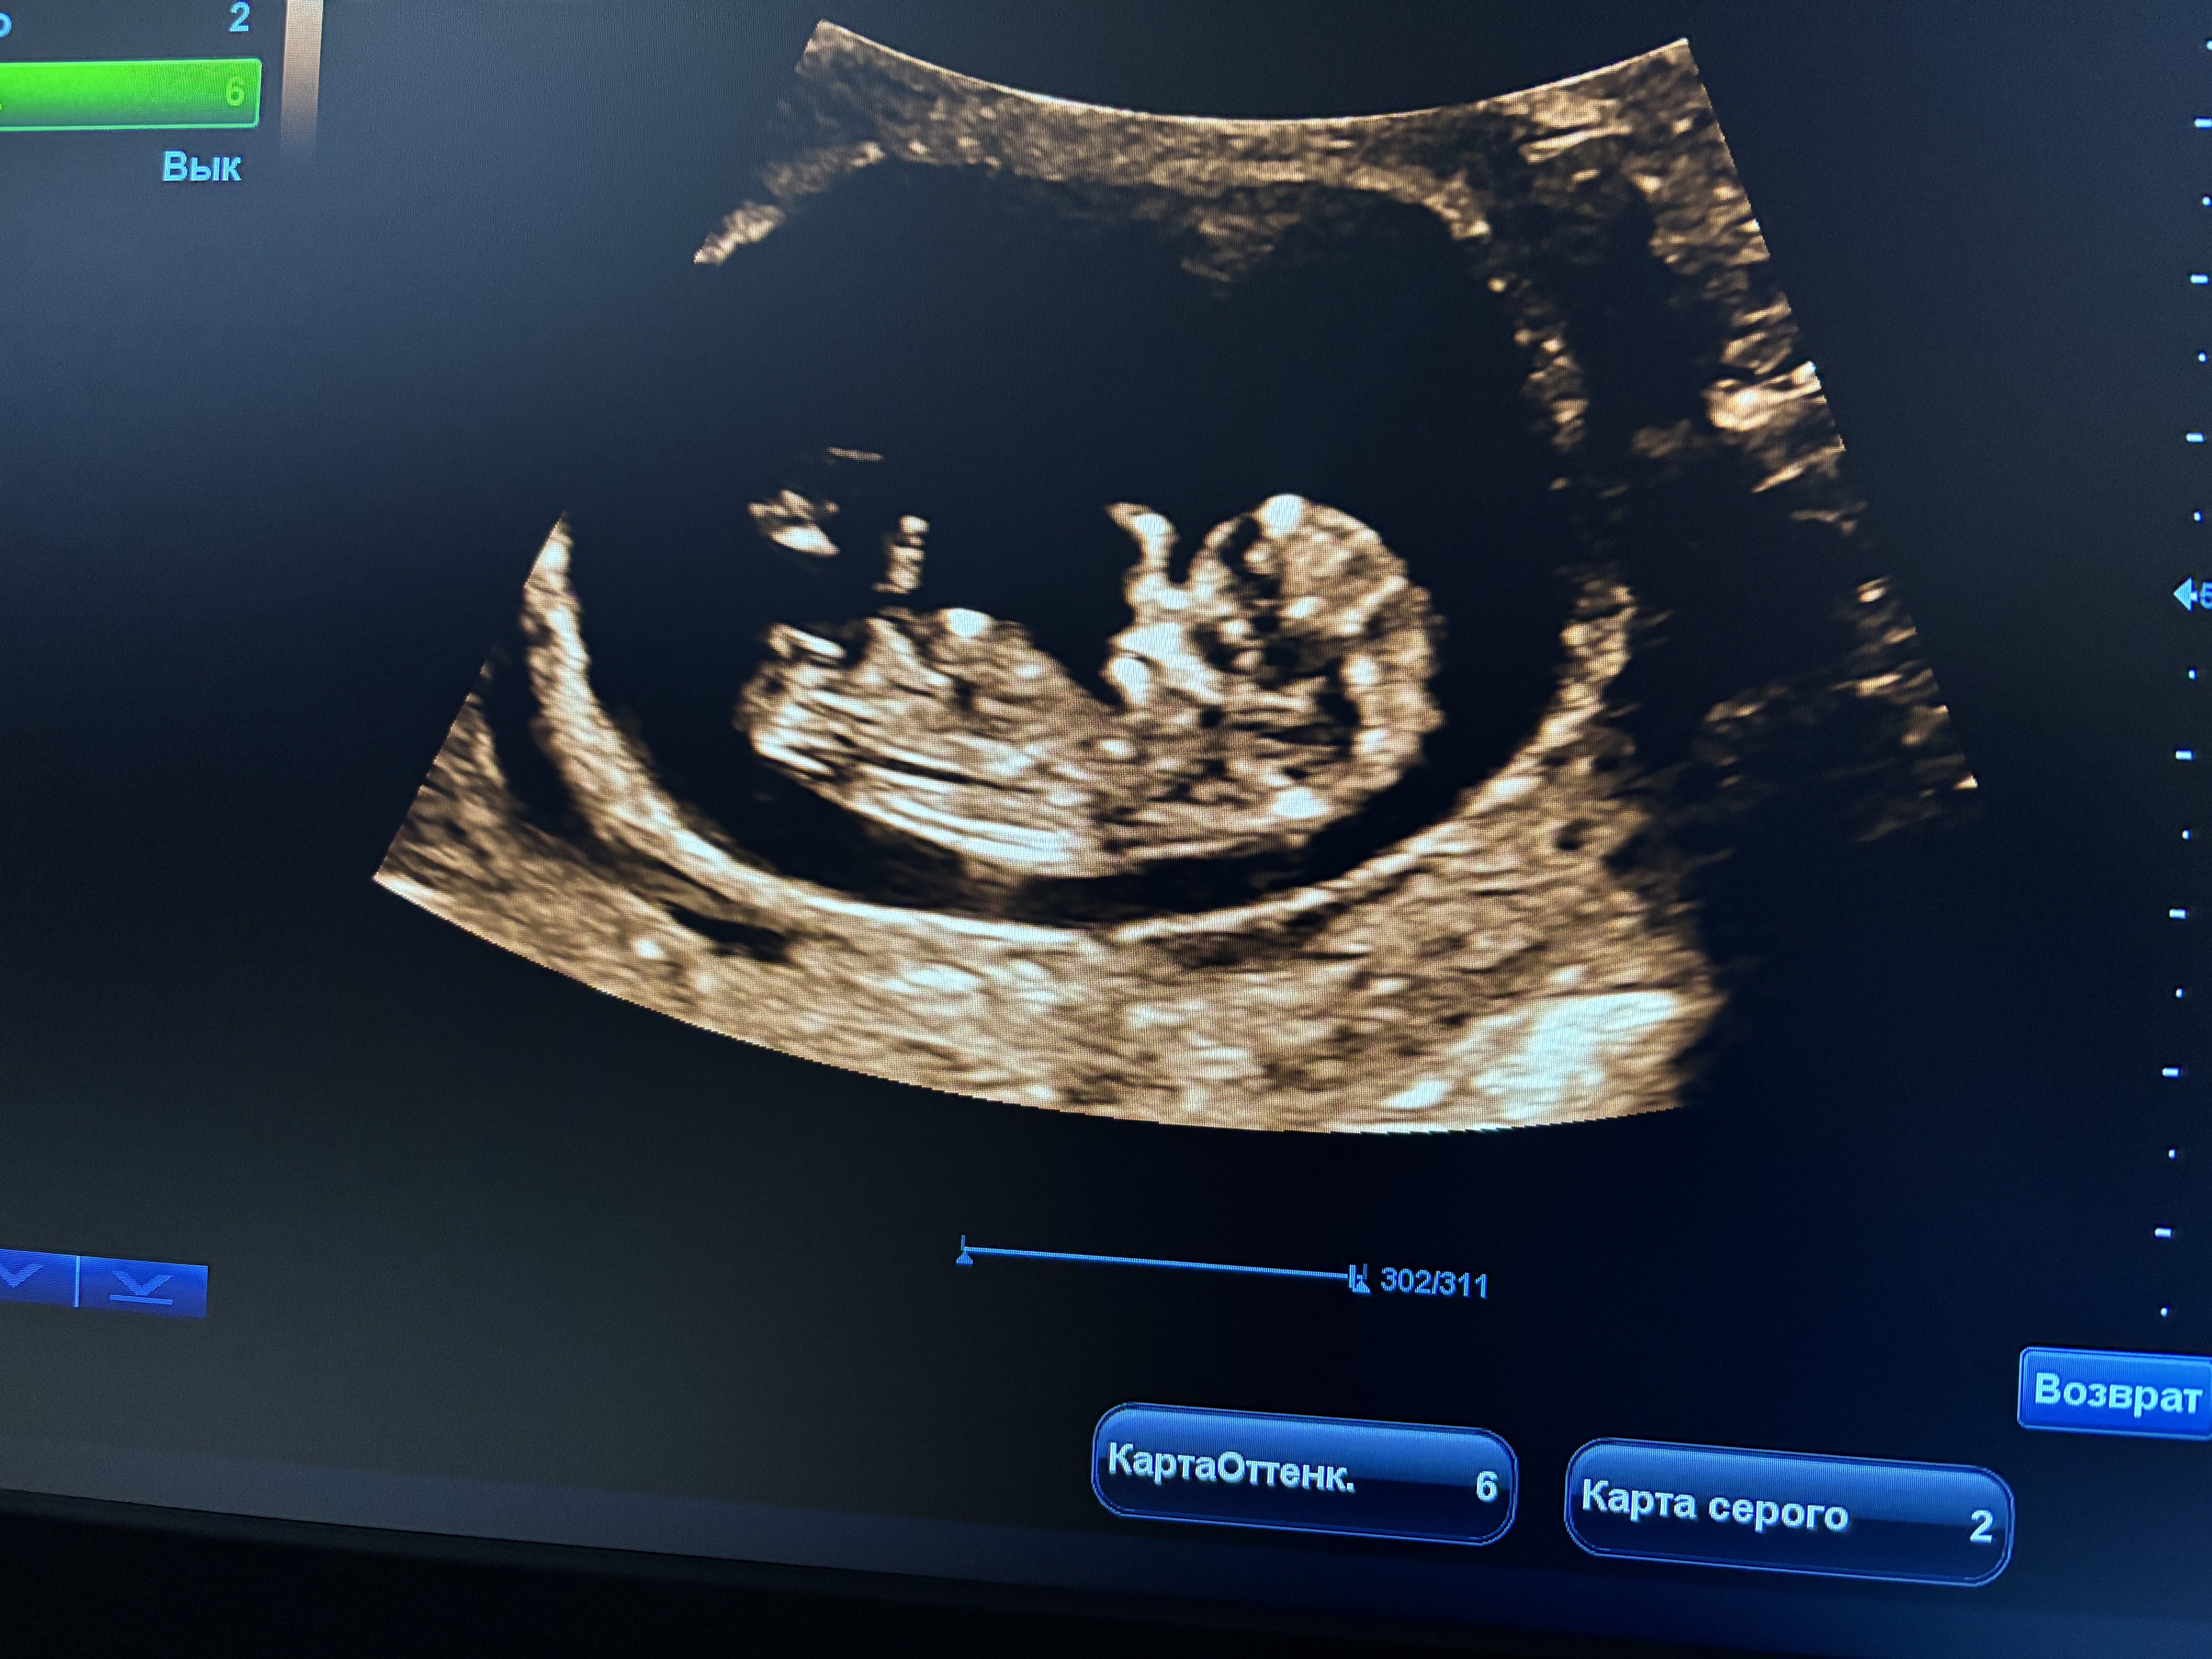

Девочки, всем привет) мальчик или девочка? На скрининге у нас очень серьезные тети, ничего не сказали)))

На девочку похоже